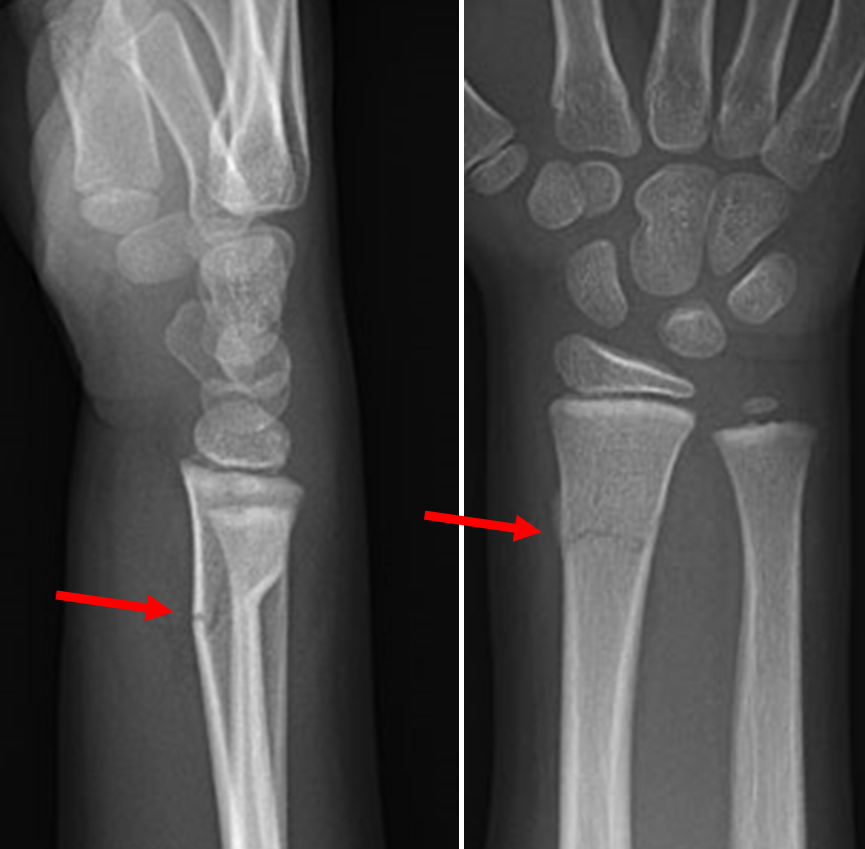

Example xray of distal radius buckle fracture:

Case courtesy of Dr Maulik S Patel, Radiopaedia.org. From the case rID: 10733